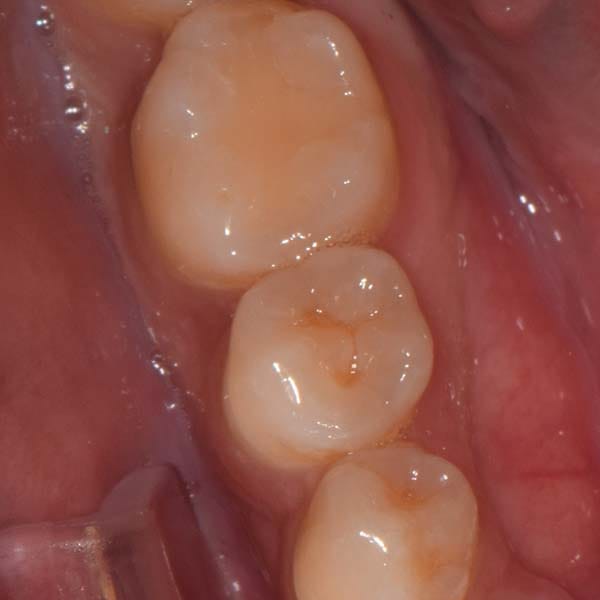

حالة رحى سفلية منطمرة و مائلة في الطرف الأيمن تم تعديلها تقويمياً و رحى سفلية مائلة في الطرف الأيسر أيضاً تم تعديلها تقويمياً